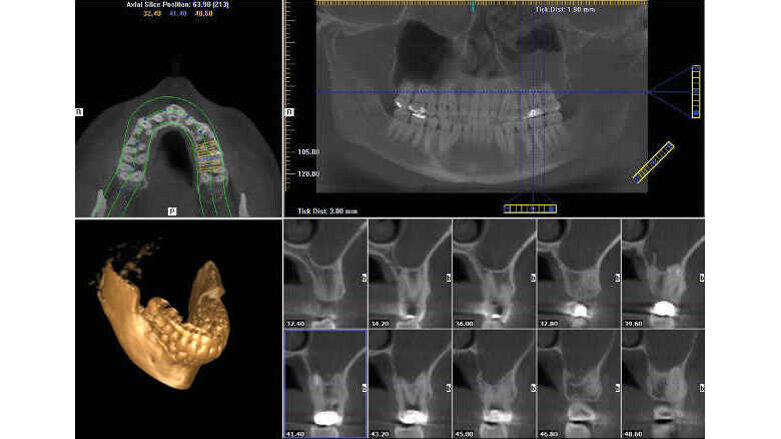

Un patient avait été adressé au cabinet en raison de problèmes associés à la fracture d’une lime. Il était pilote de ligne et se plaignait d’écoulements nasaux purulents lorsqu’il était en vol. La radiographie pré-opératoire (Fig. 1) a distinctement montré la présence de deux fragments d’une lime fracturée dans les canaux mésiaux et d’un cône traversant l’apex de la racine palatine. Après l’imagerie CBCT avec iCAT, il est apparu clairement que le sinus gauche était presque totalement rempli de liquide inflammatoire (Fig. 2) et que le cône présent dans le canal palatin pénétrait dans le sinus. Sur l’image de reconstruction multi planaire (MPR), nous pouvions également distinguer les deux fragments de lime fracturée dans les deux canaux mésiaux (Figs. 3 et 4) et aussi un autre fragment dans le sinus sans aucun contact avec le canal (Fig. 5). L’utilisation de différents filtres nous a permis de visualiser les fragments de lime (Figs. 6–9), ainsi que l’inflammation et le fragment de lime fracturée à l’intérieur du sinus. Nous avons également mieux perçu la position du cône qui émergeait du canal palatin et pénétrait dans le sinus.